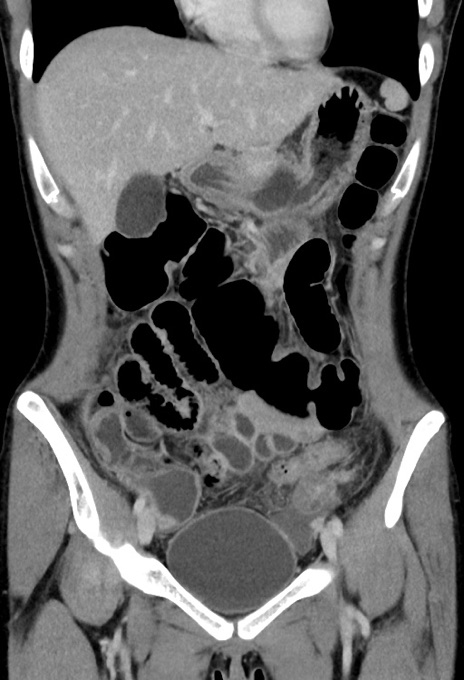

横断像

【症例】20歳代女性

【主訴】嘔吐、下腹部痛

【現病歴】昨日夕食後に嘔吐し下腹部痛が出現。本日になっても嘔吐持続し改善しないため来院。

【身体所見】意識清明、BT 37.2℃、BP 108/67mmHg、腹部:平坦、やや硬、下腹部正中から右にかけて圧痛あり、反跳痛軽度あり、tapping pain(+)。

【データ】WBC 13600、CRP 14.94